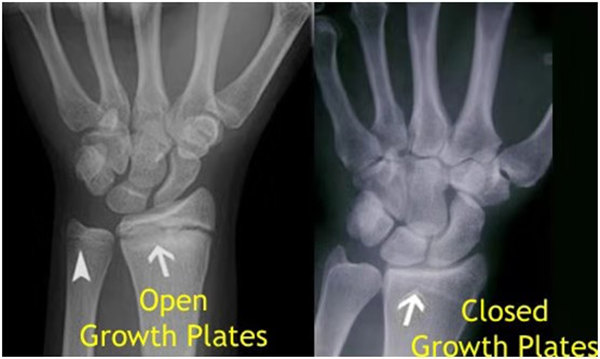

其實想要了解孩子的生長發(fā)育情況或者說孩子未來身高的趨勢,測骨齡是個好辦法。臨床上通常拍攝兒童的左手正位X光片 , 采用《中華-05》骨齡標(biāo)準(zhǔn)對手腕骨發(fā)育程度進(jìn)行骨齡評價。